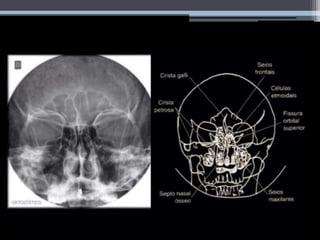

Seios Perinasais – Visão geral

Radiografia

Convencional

Método auxiliar

mais antigo no

diagnóstico de

rinossinusites

Rápido e

económico

Técnica limitada

Radiografia Convencional

Incidências

Radiográficas

Frontonaso

(Caldwell)

Mentonaso

(Waters)

Perfil Axial de Hirtz

Linhas do crânio

• - Auxiliam no posicionamento em exames de

crânio e face.

• #9 Tumores não são hiperdensos, por isso por TAC consegue-se distinguir. A TAC capta, mas a RM distingue. As variações anatómicas são importantes para uma cirurgia endoscópica, uma vez que o cirurgião pode perfurar equivocamente romper artérias, causando hemorragia. Se a extensão da sinusite for intra-orbital, conseguimos ver por TAC. Através das janelas T1 e T2, e a partir das percentagens proteicas, podemos distinguir entre sangue, fungos e secreções (quando é hiperintenso). - Método auxiliar mais antigo no diagnóstico de rinossinusites (opacificação ou velamento do interior da cavidade paranasal, níveis hidroaeres ou espessamento muscoso superior a 6-8 mm – para crianças e adultos respectivamente) -Barato (em muitas situações pode ser o método de diagnostico complementar único disponível, como no brasil- condições precárias); -Rápido; -Técnica limitada (pouca qualidade de imagem). Raio x – direita e TAC a surgir depois á esquerda.